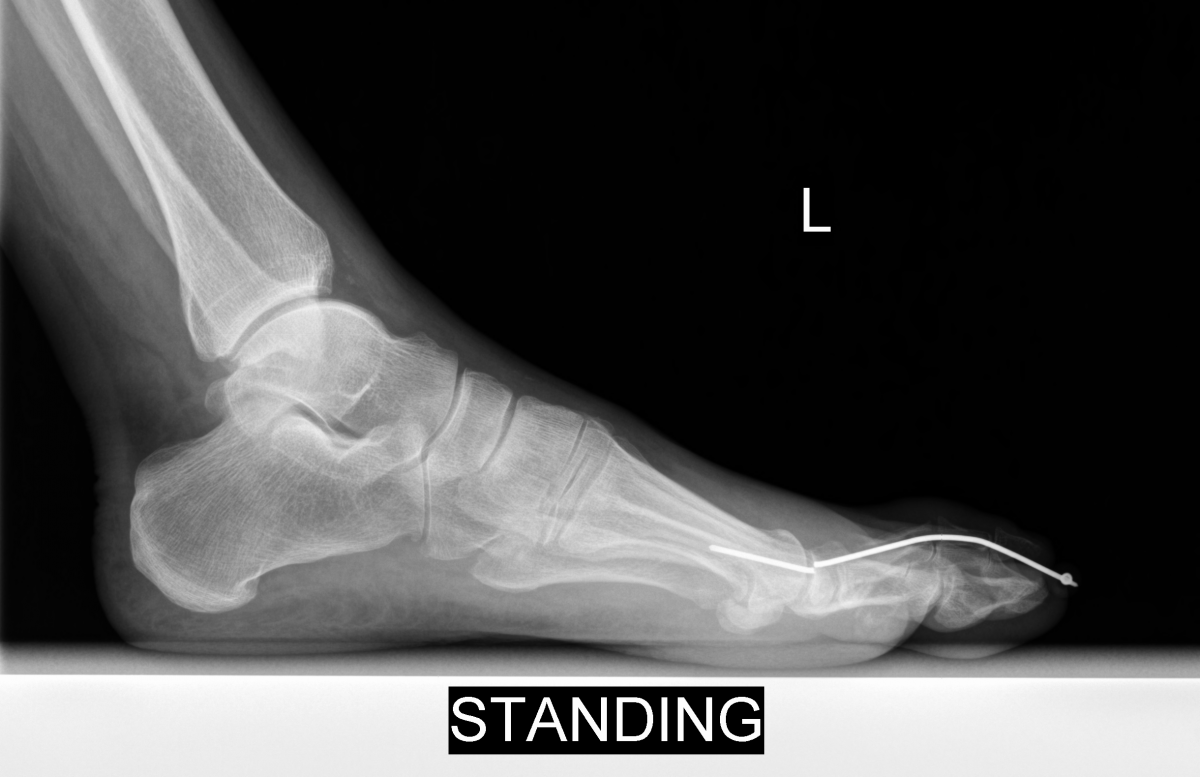

Implant sizing is important to avoid complications. Many of the newer hammertoe implants feature expanding “memory” metals, which not only aid in arthrodesis compression but also lend stability by expanding within the intramedullary canal. When using screws or K-wires, the surgeon must ensure that the diameter of the implant is appropriate for the diameter of the phalangeal intramedullary canals. Otherwise, rotation or residual flexion can occur as one can see in the photo above. In this example, the diameter of the embedded K-wires was too small and allowed for flexion and toggling within the intramedullary canal as well as loss of correction.

Furthermore, poor patient adherence can be detrimental to any procedure and contribute to hardware breakage and procedure failure. The left photo shows a foot two weeks after the patient had a well positioned and fixated proximal interphalangeal arthrodesis. However, by the four-week follow-up, the patient had returned to regular shoes against medical advice and returned to full duty at his job as a construction worker, contributing to implant failure.